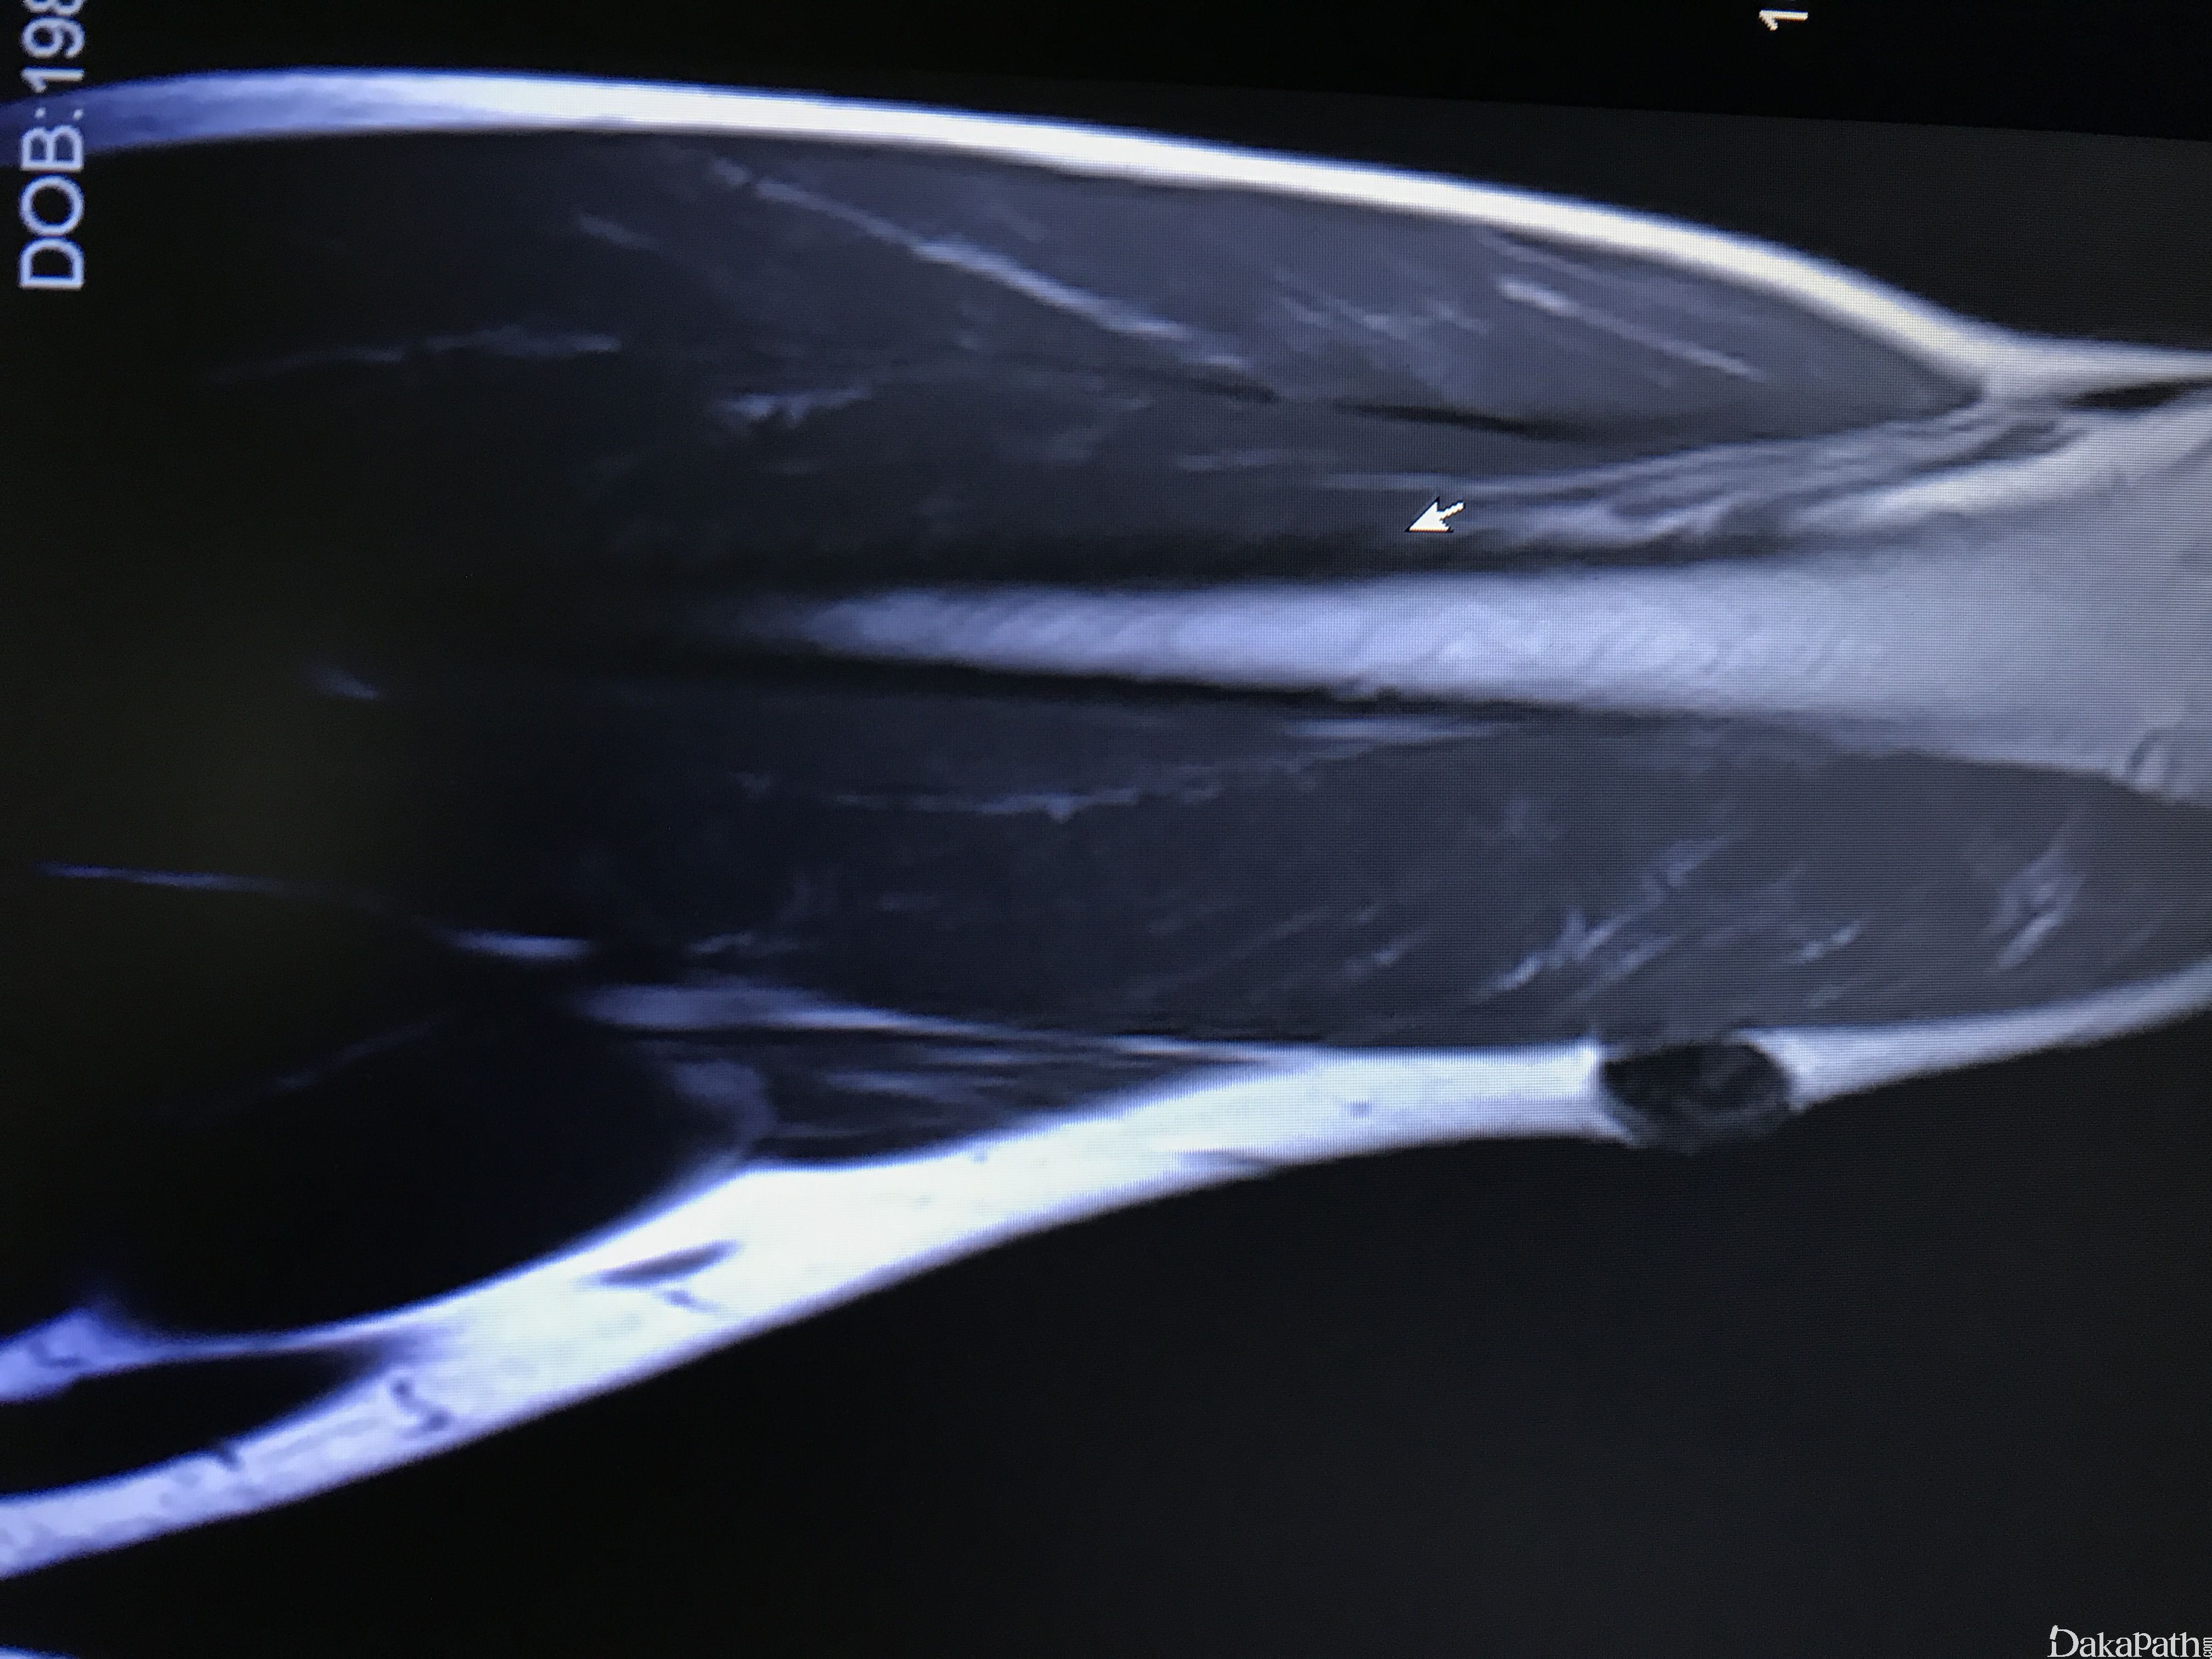

发病部位: 下肢>上肢>头颈部和躯干

由 Carter 等于 2014 年首先报道并命名,均发生于成人,发病年龄 20 到 76 岁(平均 38 岁),约半数<30 岁,男女比例大致相等;肿瘤大多数表现为肢体皮下组织内、筋膜上缓慢生长的无痛性肿物,与肌肉组织无粘连,下肢(大腿,膝关节周围)明显好发于上肢,罕见可发生于头颈部或躯干;

直径从 1.5 至 10cm 不等 (平均约 4.0cm),质实,切面灰黄灰褐色有光泽;